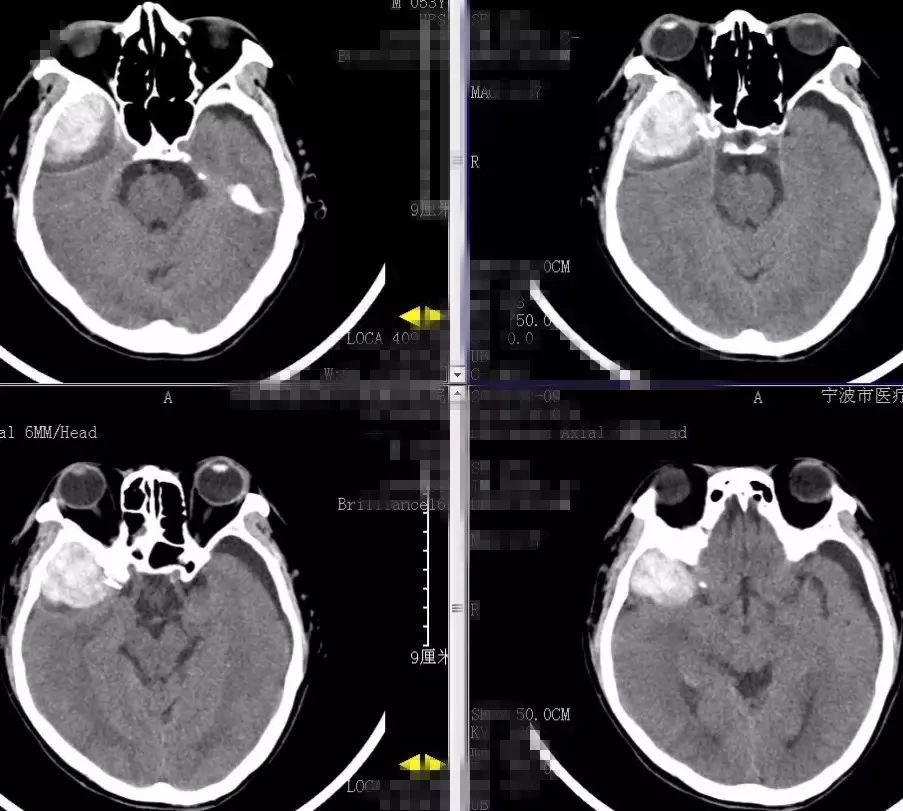

辅助检查:2018-1-10复查头部及胸部CT:右颞部硬膜外血肿。右侧颞骨、颧弓骨折,右侧颅底多发骨折(图1)。右侧液气胸,胸腔引流管在位。右侧多发肋骨骨折。右肱骨正侧位片:右侧肱骨下端粉碎性骨折。

图1. 2018-1-10入院时头CT:右颞部硬膜外大血肿。右侧颞骨、颧弓骨折,右侧颅底多发骨折。